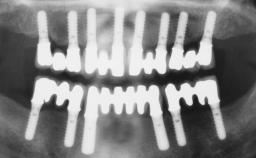

Immediate Implant Placement and Immediate Provisionalization with a Prefabricated-Shell Provisional Crown

In this case, Arndt Happe describes how he achieved a stable outcome at 5 years by giving careful attention to the coronal aspect of the transmucosal area of the provisional, creating a slim emergence profile.

A healthy 31-year-old female patient presented with a failing maxillary left lateral incisor crown. The crown regularly loosened, and the remaining tooth was neither restorable nor rational to treat. The patient had a high smile line, a medium soft tissue biotype with a compromised mesial papilla (shorter than the contralateral one), and a horizontal scar in the buccal soft tissue as a result of past periapical surgery.

Timing of placement Immediate Placement (extraction sockets) (Type I)

Loading Protocol Immediate